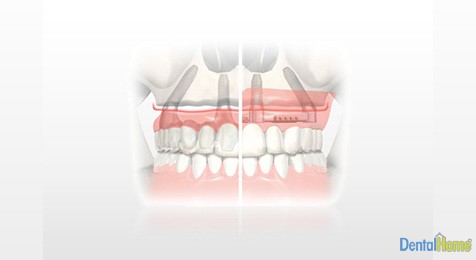

All On Four Implants, are implants used for cases where patients have had full dentures and have permanent issues with mobility, which prevents them from chewing all foods easily and mispronounce words, that is why this system has 4 completely fixed implanted dentures that allows the client to bite and speak with more confidence, improve self-esteem. Also this system improves dental and facial aesthetics while being able to enjoy food more.

This type of dental implant is perfect for use with clients who want to regain all of the lost teeth of one jaw or who do not have enough bone in some areas. Since this process is very similar to how single implants are used, it provides optimal support for a fixed dental bridge which can be made and in use in just a few days after the procedure.